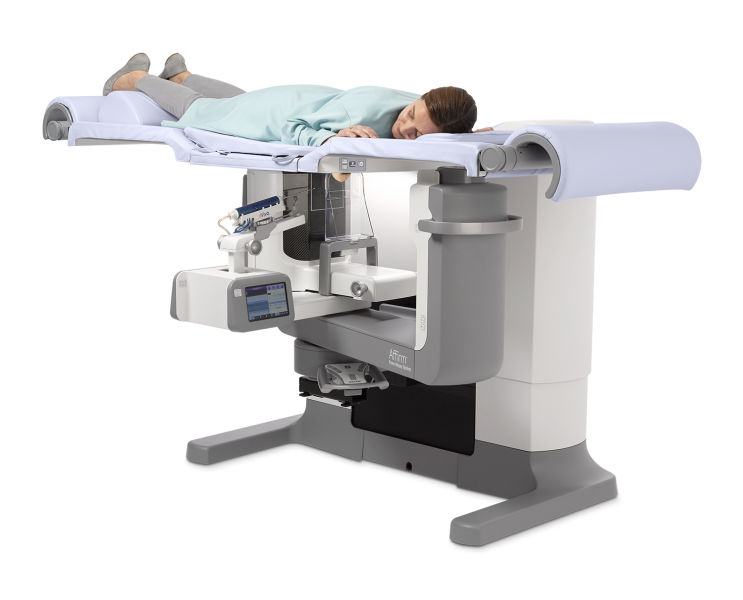

GE Healthcare and Premier Inc. have announced a collaboration to develop a model to bring a same-day breast cancer diagnosis and treatment model to the United States. A similar model has already proven effective at the Gustave Roussy Cancer Campus in France.